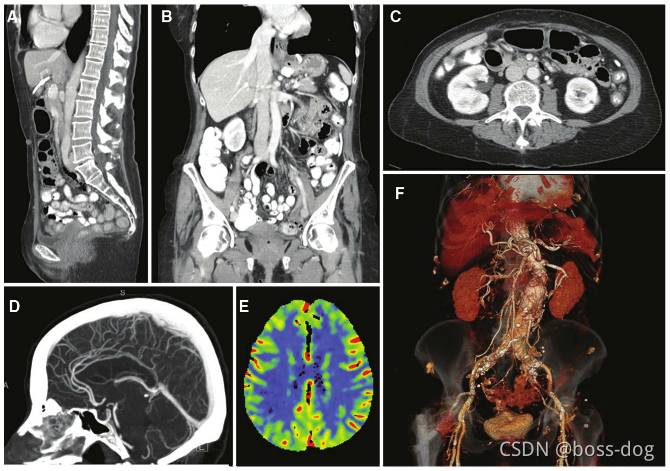

Computed Tomography(CT成像)

A: Sagittal;(矢状位)

B: Coronal;(冠状位)

C: Axial;(轴向的)

D: CT angiography of the head;(头部CT成像,通过静脉注射碘对比剂吸收X光)

E: Blood volume;(头部供血状况)

F: Pseudocolored 3D organ segmentation(三维的器官分割,用来进行体积或距离的测量)